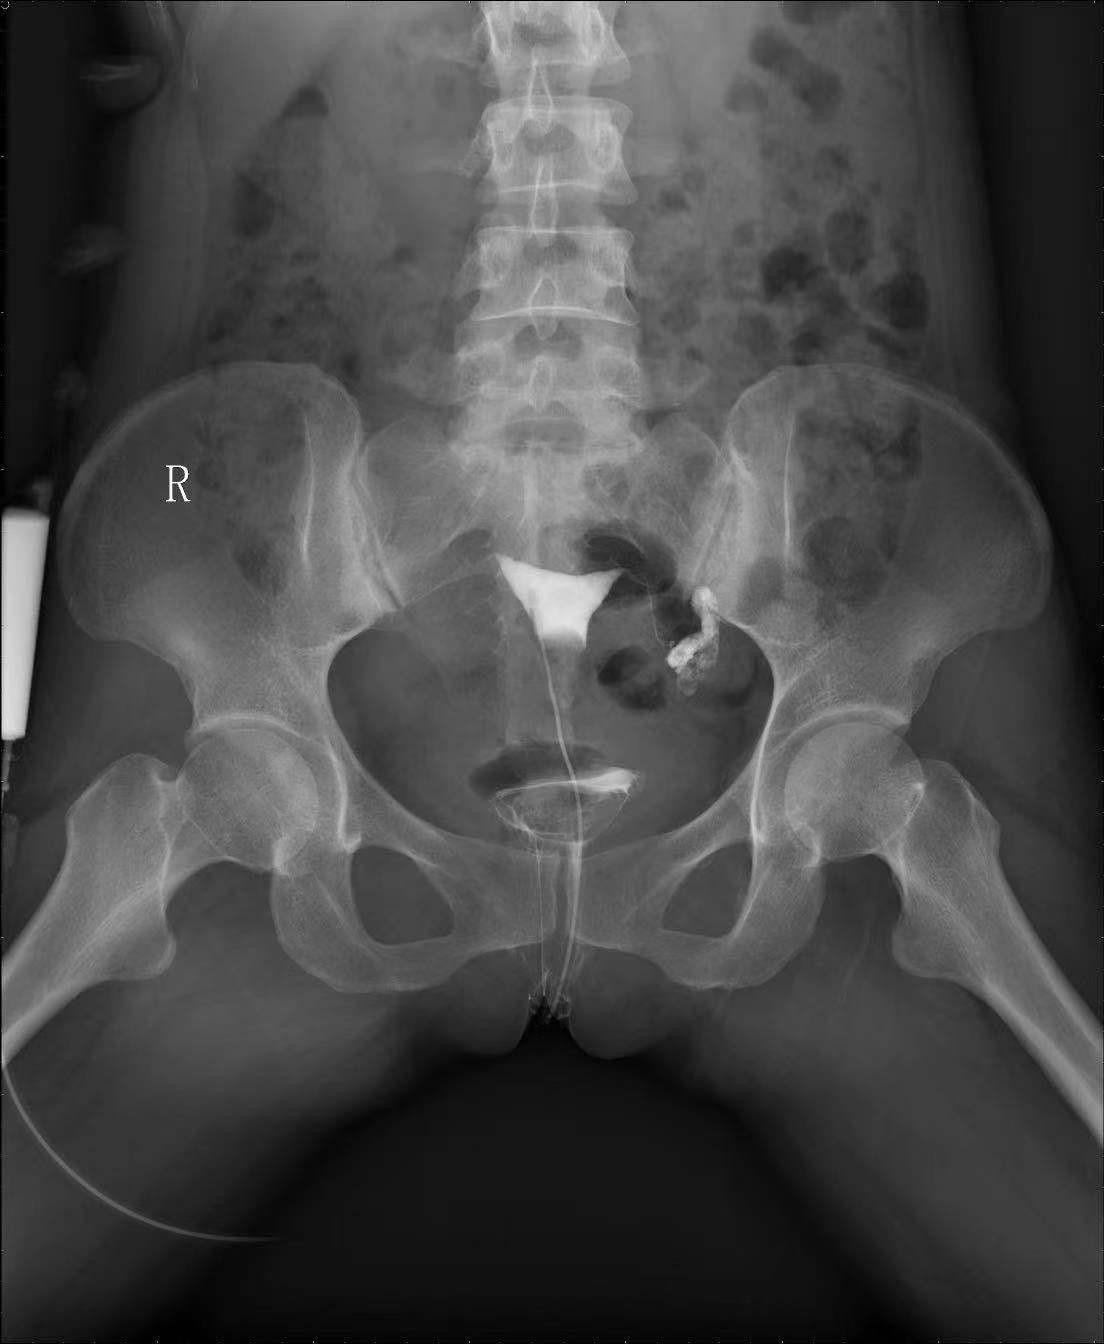

门诊子宫输卵管碘造影是通过向宫腔内注入碘伏醇造影剂,在X光下动态地观察造影剂在宫腔及输卵管的流动情况,实时立体的判断宫腔形态、输卵管管腔通畅性及其形态走行、以及造影剂盆腔弥散情况等。子宫输卵管造影已在妇产科临床中,特别是不孕不育患者的诊治中取得较好的效果,是一种安全、微创的检查新技术,能够快速、可重复地评价输卵管通畅性。

患者造影报告指出左侧输卵管远端(伞端)粘连、积水,左侧输卵管未显影。吴萍医生结合患者既往左侧输卵管妊娠,曾行腹腔镜下左侧输卵管切除术病史,以及患者阴道超声,性激素结果,给出患者治疗建议。

该患者左侧输卵管远端扩张呈长形囊状,造影剂积聚于输卵管内,弥散平位片见盆腔内仍无造影剂。